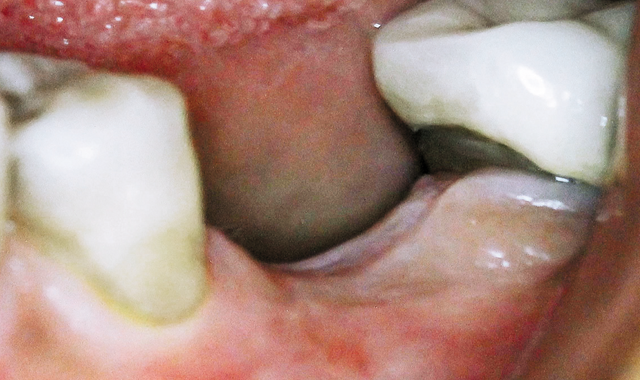

Fig. 2 Extraction site two months later.

Two months later, the extraction site was prepared for placing an implant (Fig. 2).